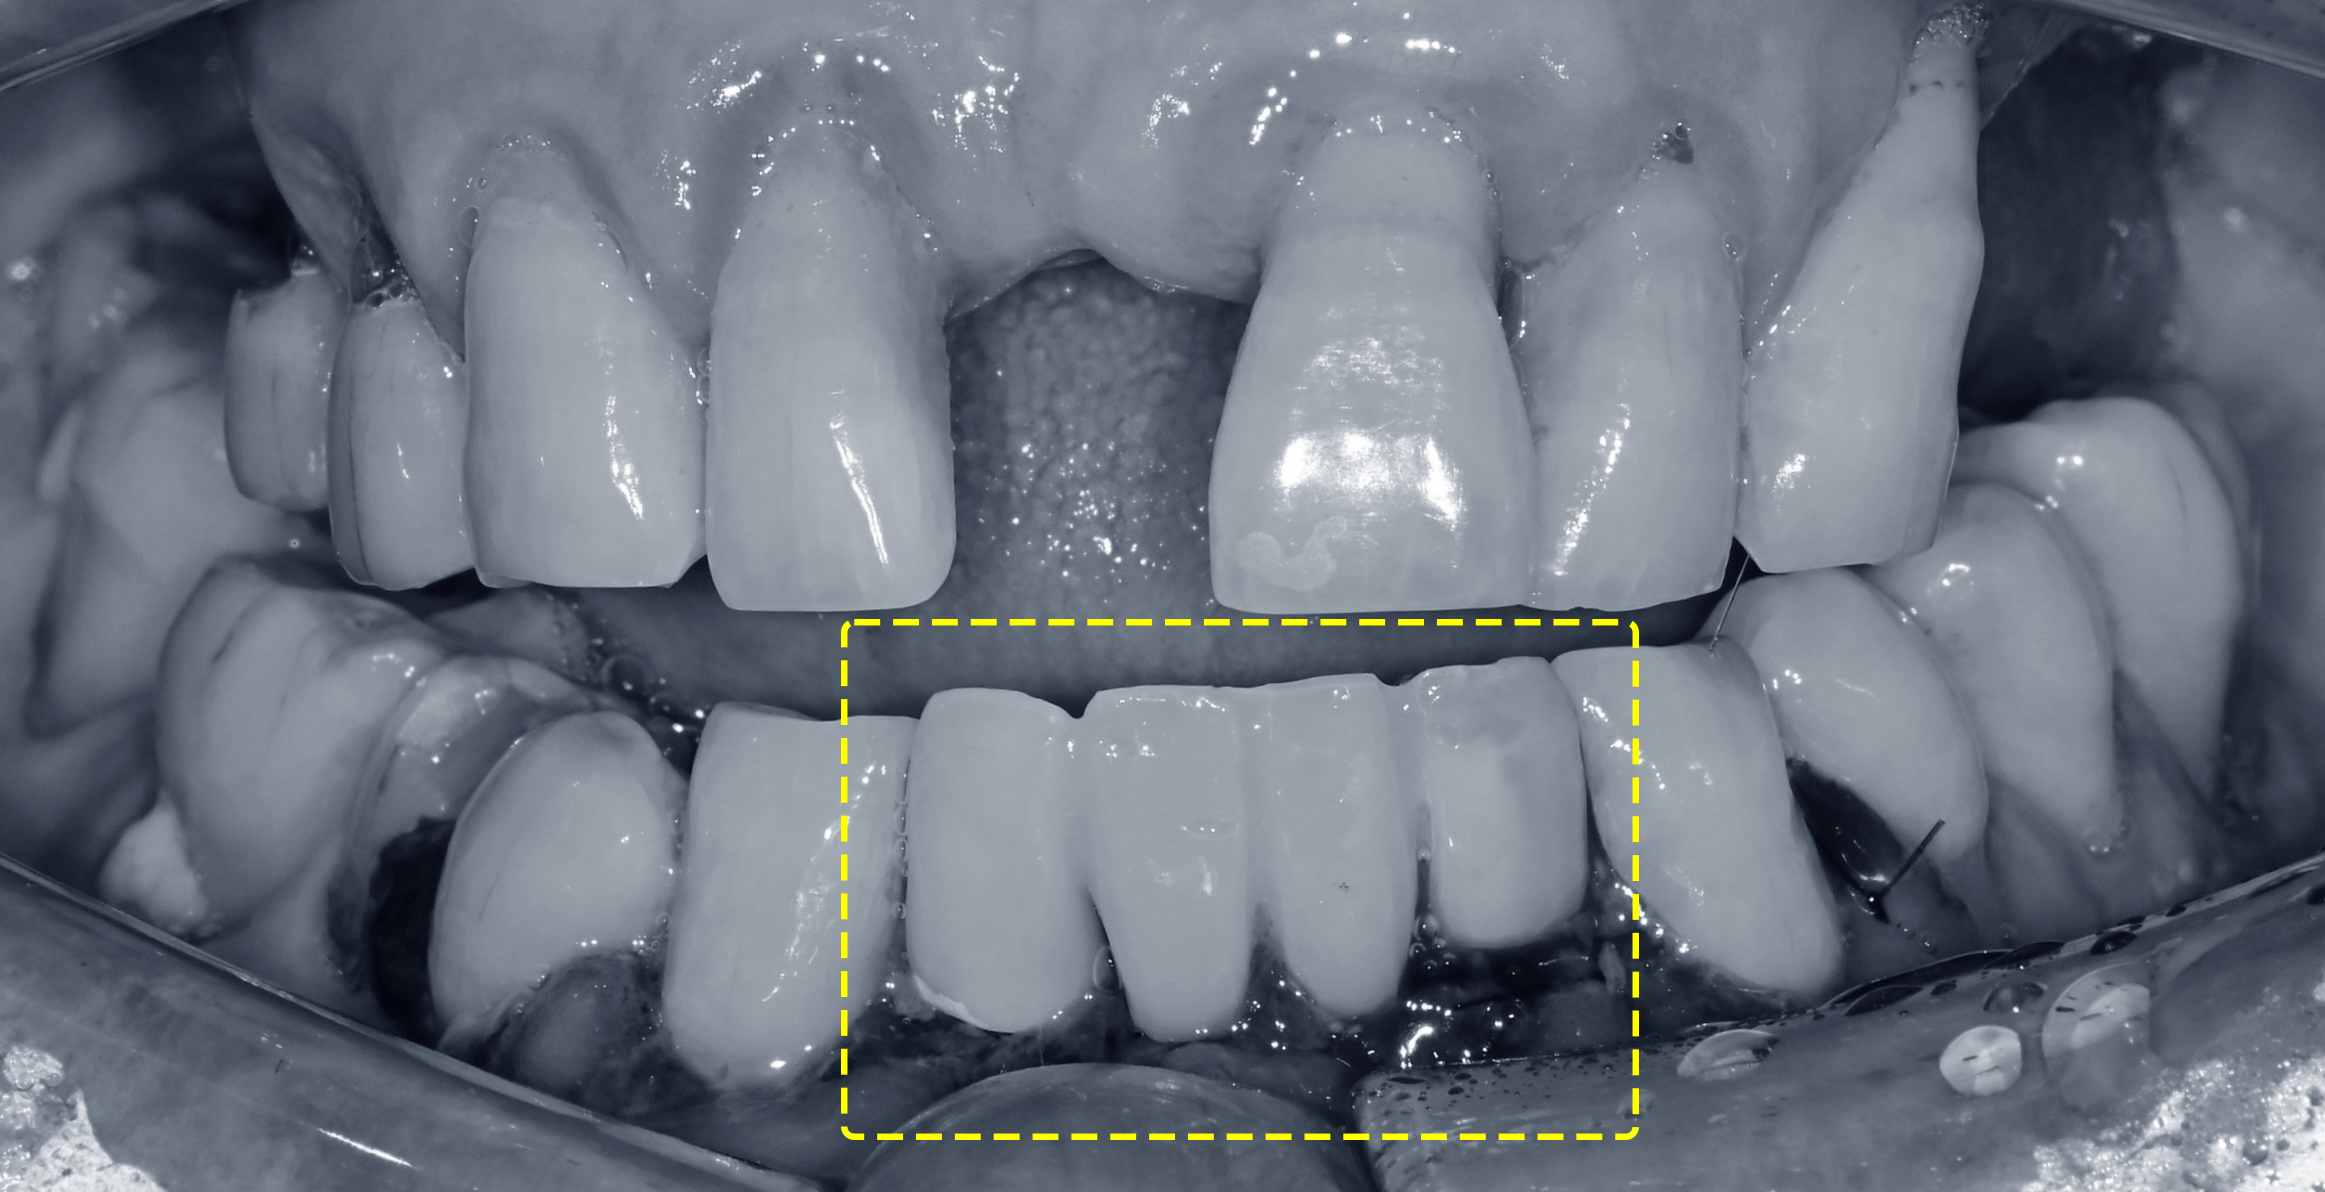

• STEP 01

수술부위